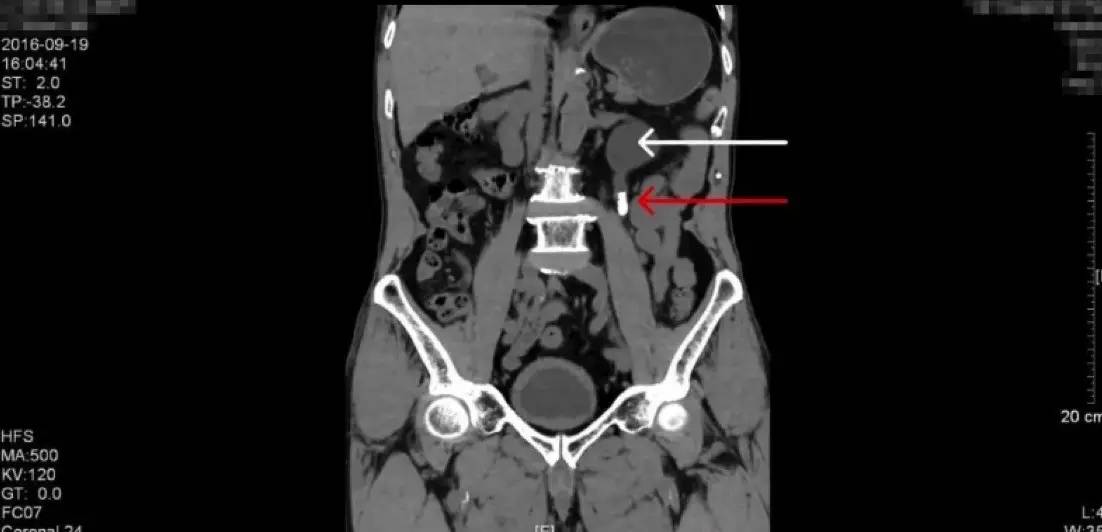

上图为CT平扫的三维重建图像(红色箭头为结石,白色箭头为积水肾)

泌尿系CT平扫是泌尿系结石手术前的必备检查,因为它可以清晰的显示各个器官的毗邻结构和结石的位置大小,并且可以做图像的三维重建。本例患者的CT图像如上,结石同样显示为白色强化,是身体的横截面,这里结石看起来是圆形的,是结石的横截面。